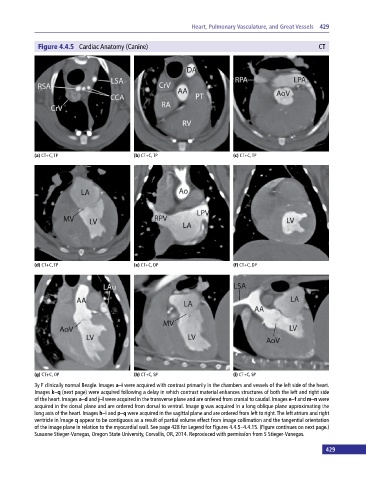

Figure 4.4.5 Cardiac Anatomy (Canine) CT

(a) CT+C, TP (b) CT+C, TP (c) CT+C, TP

(d) CT+C, TP (e) CT+C, DP (f) CT+C, DP

(g) CT+C, OP (h) CT+C, SP (i) CT+C, SP

3y F clinically normal Beagle. Images a–i were acquired with contrast primarily in the chambers and vessels of the left side of the heart.

Images k–q (next page) were acquired following a delay in which contrast material enhances structures of both the left and right side

of the heart. Images a–d and j–l were acquired in the transverse plane and are ordered from cranial to caudal. Images e–f and m–n were

acquired in the dorsal plane and are ordered from dorsal to ventral. Image g was acquired in a long oblique plane approximating the

long axis of the heart. Images h–i and p–q were acquired in the sagittal plane and are ordered from left to right. The left atrium and right

ventricle in image q appear to be contiguous as a result of partial volume effect from image collimation and the tangential orientation

of the image plane in relation to the myocardial wall. See page 428 for Legend for Figures 4.4.5–4.4.15. (Figure continues on next page.)

Susanne Stieger‐Vanegas, Oregon State University, Corvallis, OR, 2014. Reproduced with permission from S Stieger‐Vanegas.